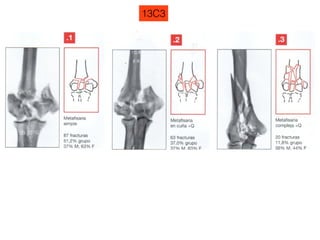

13C3